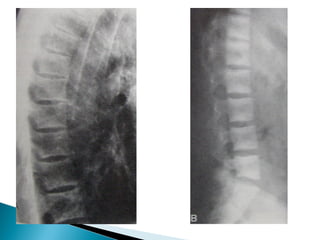

•   Subperiosteal cortical resorption of middle phalanges

•   Vertebral collapse

Osteoporosis • Subperiosteal cortical resorption of middle phalanges • Vertebral collapse • Brown tumors • Renal calculi,Nephrocalcinosis • Chondrocalcinosis